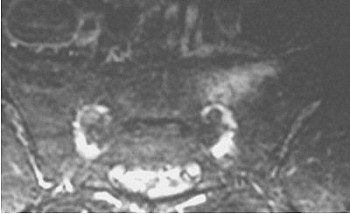

| MRI of sacrum in an ultramarathoner showing abnormal signal of a stress fracture. Image courtesy of Duke University Medical Center, Durham, NC. |

"All of our (runners) were training for ultramarathons -- 50K, 50-mile, and 100-mile races. Three had findings on physical exam of regular lumbar spine disease, and it was attributed to having sciatica," she said.

However, Major continued, "when the MR was done in one person, a sacral stress fracture was found. The others had MR also, and they too had sacral stress fractures. All along they’re thinking they have disc disease, and so it’s probably occurring much more commonly than we think. Making the diagnosis is key, and it’s a very easy diagnosis to make with MR."